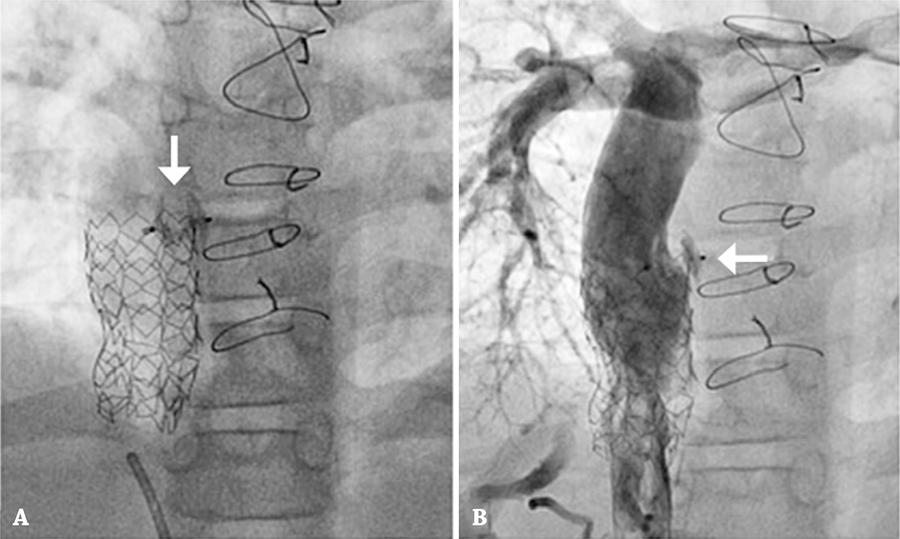

Figure 4

Occlusion of fenestration. (A) Amplatzer Duct Occluder II 5×6 mm (AGA Medical Corporation) (arrow). (B) Control angiography demonstrating no flow at the prosthesis site (arrow).